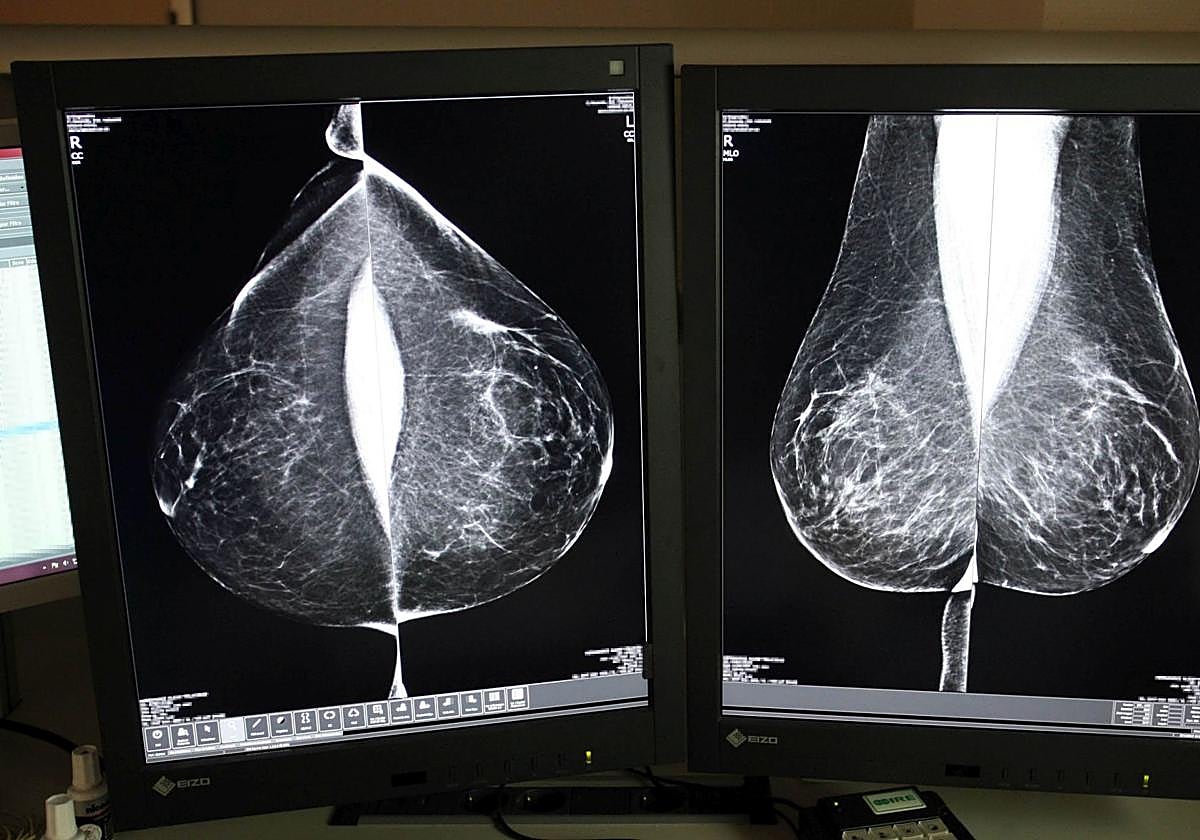

Estudio de una mamografía digital en el hospital de Valladolid. Rubén Cacho

La Consejería de Sanidad vuelve a externalizar el servicio de doble lectura e informe de mamografías este año para dar respuesta a la alta cobertura del Programa de Detección Precoz de Cáncer de Mama. La licitación, conocida por Ical, asciende a 1,38 millones de euros por un año, con la posibilidad de prórroga hasta un máximo de dos años, lo que elevaría el valor estimado del contrato a más de tres millones de euros. La financiación del contrato aprobado hasta la fecha se distribuye en dos anualidades: 929.200 euros en 2025 y 450.800 euros en 2026.

Desde su puesta en marcha en 1992, el programa se basa en el sistema de doble lectura, un protocolo que establece que cada mamografía sea evaluada por al menos dos radiólogos, de forma independiente, aumentando así la fiabilidad de los diagnósticos. Sin embargo, aumenta la carga de trabajo y plazos, motivo por el cual Sacyl ha optado, de nuevo, por externalizar el servicio al que el año pasado dedicó casi cuatro millones.

En 2023, último dato disponible, se realizaron un total de 122.193 mamografías, de las que 7.503 (un 6,14 por ciento) tuvieron resultado sospechoso positivo y fueron derivadas a Atención Hospitalaria para realizar el diagnóstico final. Por provincias, el porcentaje de pacientes derivadas osciló entre el 3,7 por ciento de Zamora y el 9,9 por ciento de Soria.